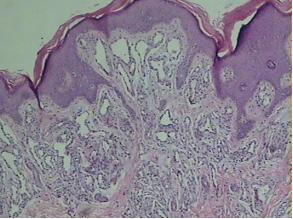

为什么预防血管瘤要从孕妇做起?我们先来了解血管瘤是怎么形成的。混合型血管瘤早在胚胎发育时期就已经形成了,它是由大量增生的血管所构成,为常见的软组织肿瘤。虽然发生血管瘤的婴儿中有10%有家族史,但它并不是一种遗传病。目前发生原因不明确,有研究认为可能与胎儿内原基细胞向内皮细胞转变时发生基因突变有关系。